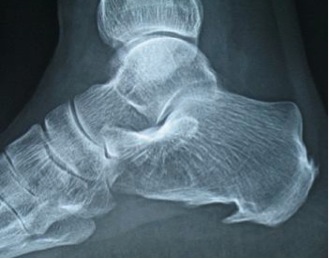

El espolón calcáneo es una excrecencia espiculada en la cara inferior del hueso calcáneo que también produce dolor en el talon. No es una enfermedad, sino un hallazgo radiográfico que puede aparecer en las talalgias.

Se trata de una osificación situada en la superficie del hueso calcáneo, que cuándo se complica con inflamación de la fascia (fascitis plantar) cursa con dolor.

El crecimiento del espolón calcáneo es muy lento, de manera que cuando lo descubrimos en un paciente que acude a consulta por una talalgia lleva ya varios años desarrollándose.